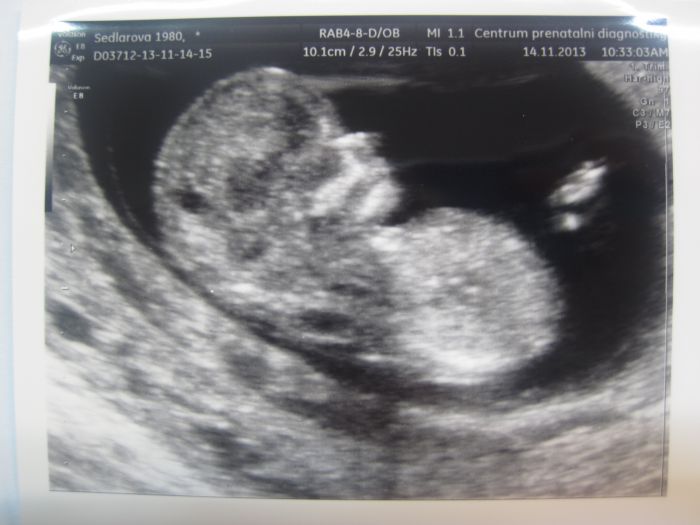

Tak tady je ta fotka.

Ahoj, tak jsme dorazili z toho screeningu. Takže podle UZ je zatím vše v pořádku, má vše co má mít, velikostně odpovídá, takže TP 26.5. Prcek nespolupracoval, nechtěl se otočit, takže v pulce jsem se šla zase projít, aby se pootočil a ukázal nos. Akorát jsem byla u dokroktorky na kterou si celkem stěžují, že není moc příjemná, a teda nebyla. Hrozně ji vadil malej, že ji ruší. Po té přestávce jsem tam už šla sama a to byla přijemnější, kontrolovala to všechno znovu a už to i vysvětlovala. A co to bude nechtěl ukázat, překřižil nohy a nechtěl se hnout. Ale říkala, že tam něco zahlédla, a že to vypadá spíš na kluka, ale ještě pořád můžu doufat v holčičku. Výsledky krve budou odpoledne, tak dám vědět.

[389300] krásná fotečka

[389300] Krasny profil!